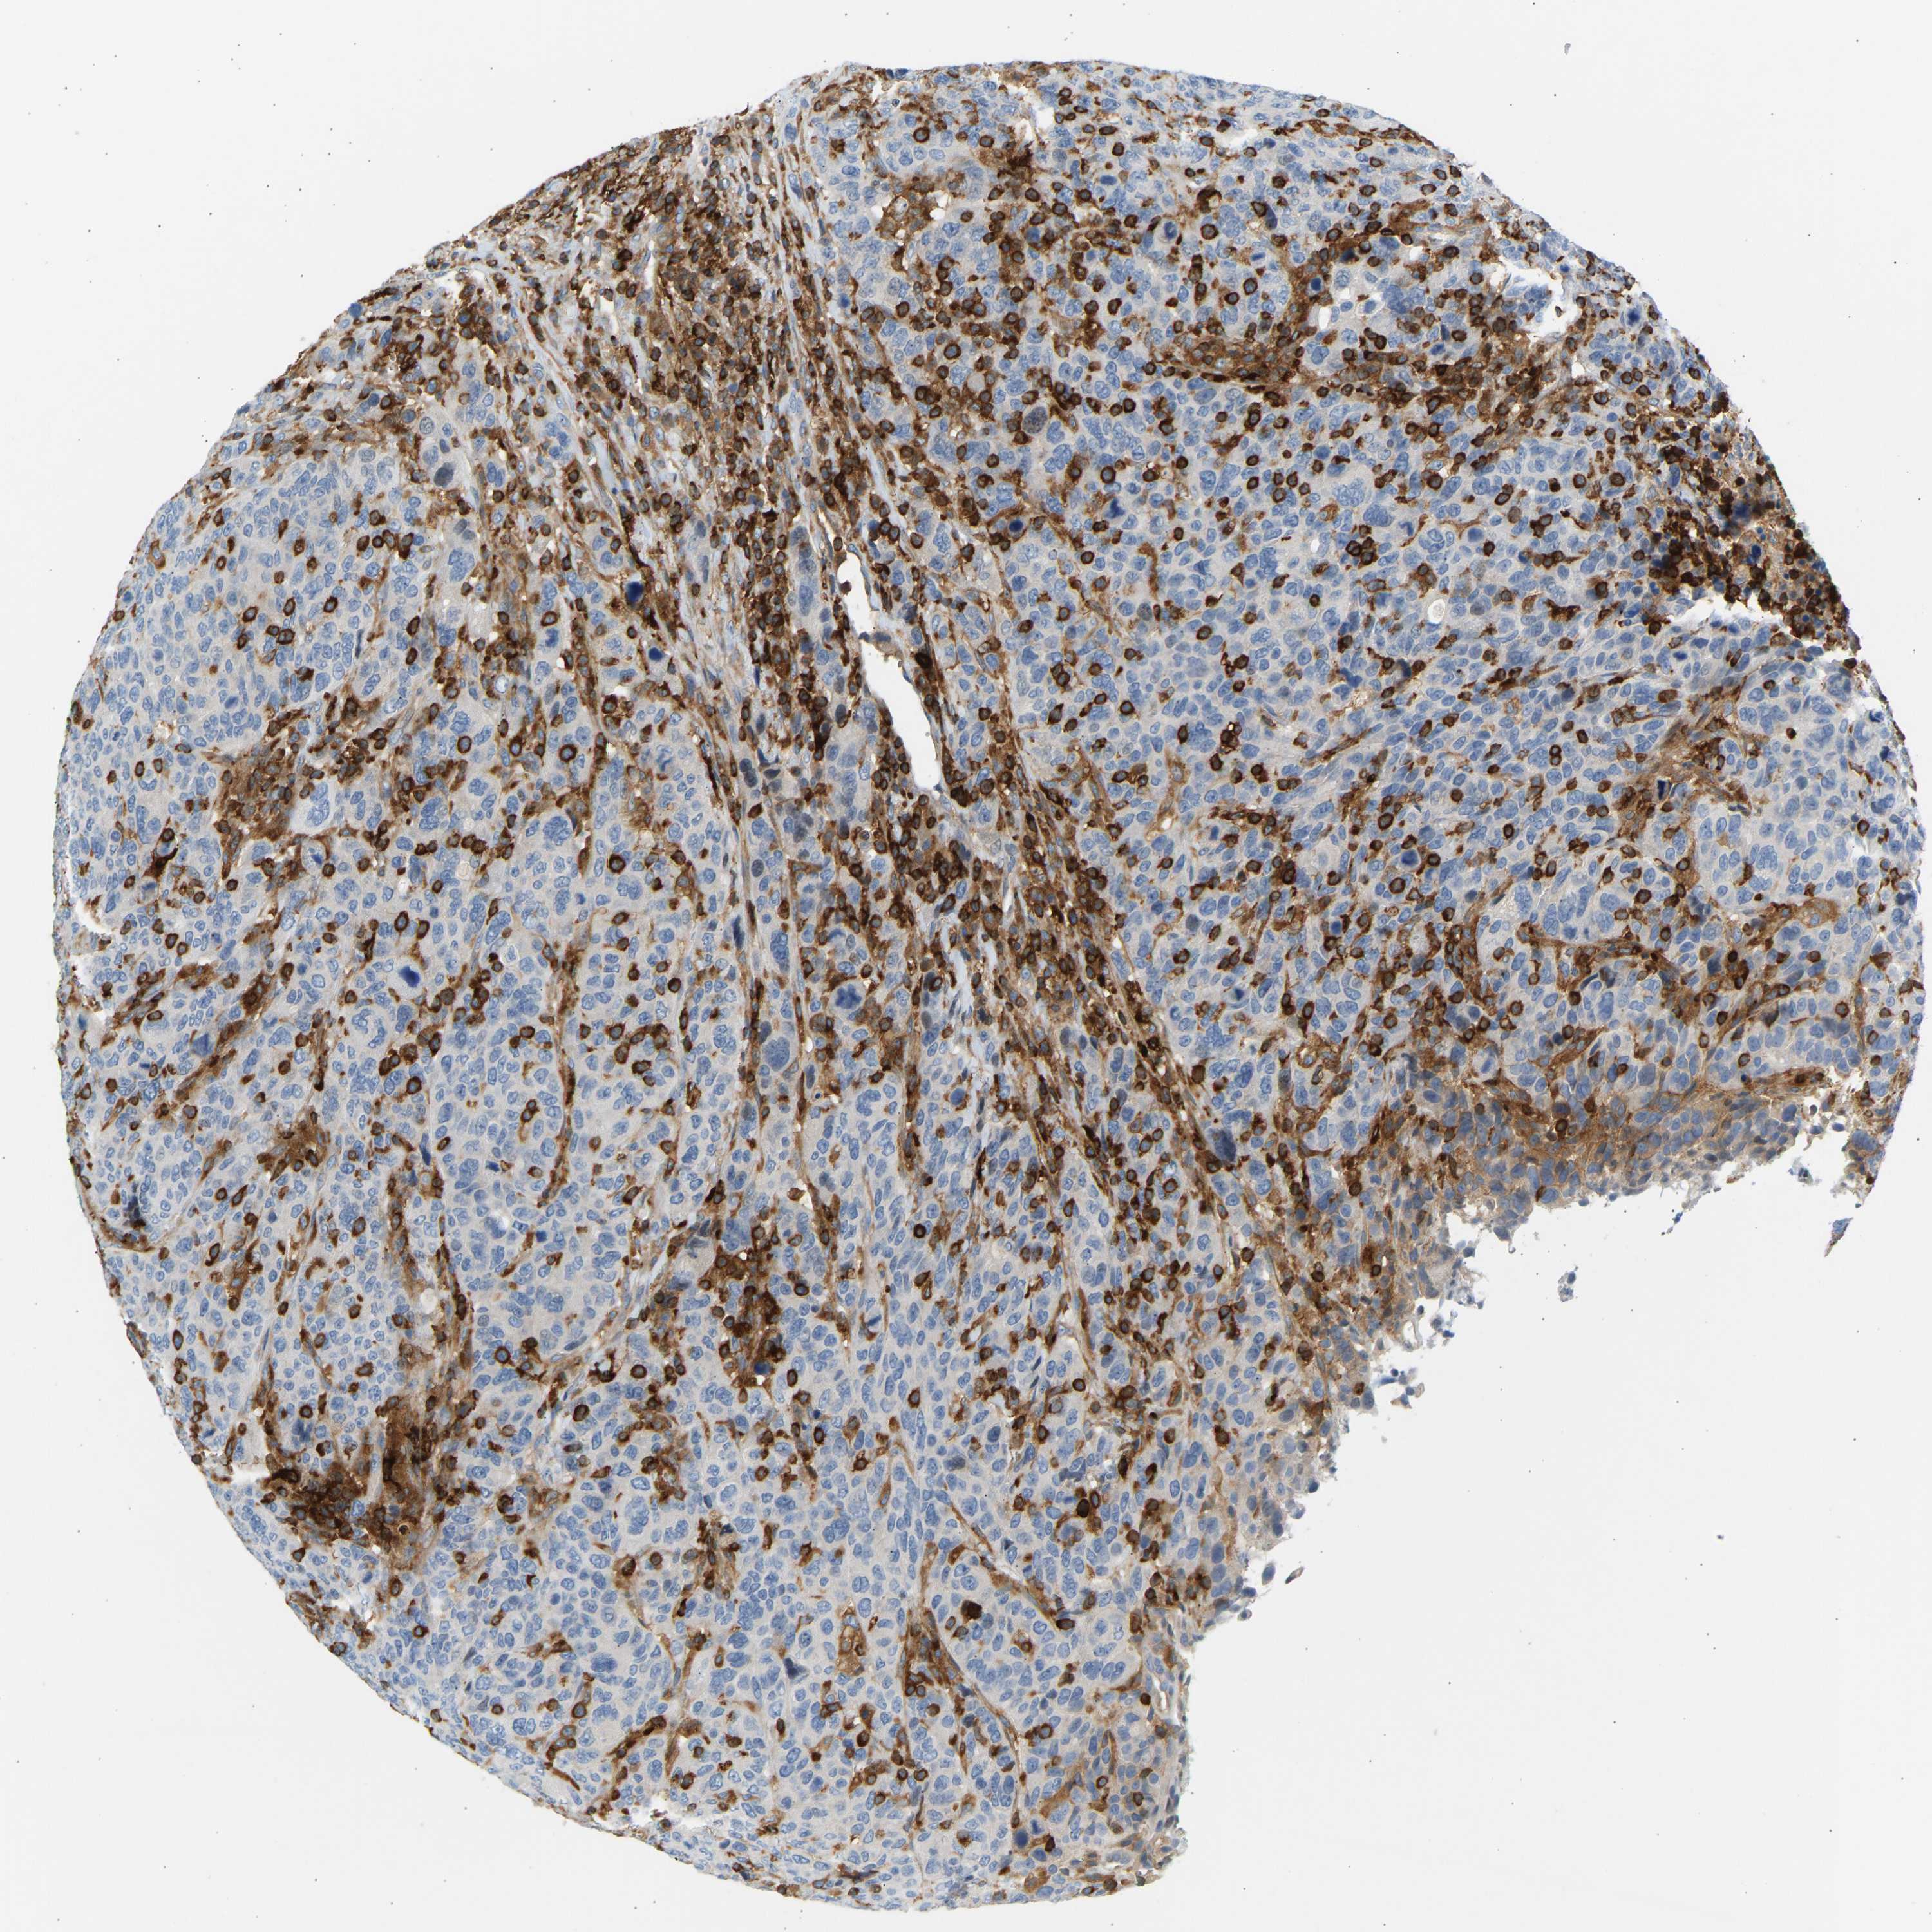

CANCER BREAST CANCER Show tissue menu

BRCA TCGA BRCA VALIDATION PROTEIN EXPRESSION

Breast cancer

Human cancer